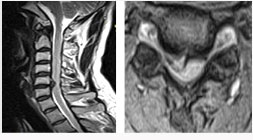

척추관 협착증의 방사선 소견